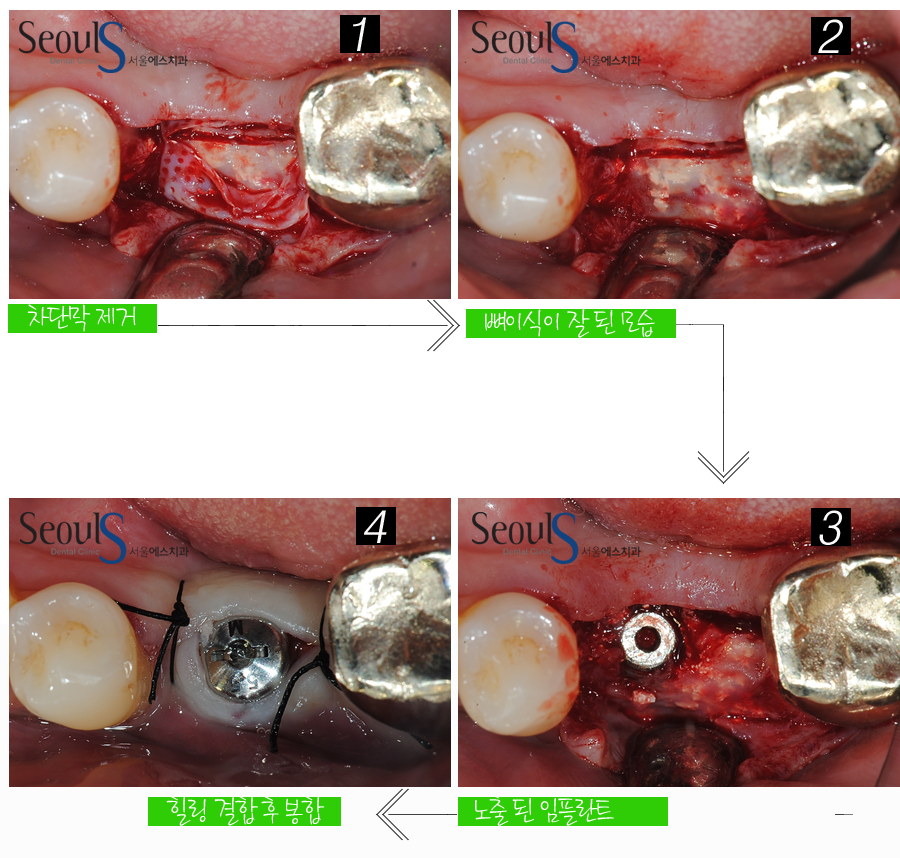

2차 수술을 진행하고 있는 모습입니다

잇몸을 열고 차단막을 제거한 후 임플란트를 노출시키는 수술로

원래는 잇몸을 열고 차단막을 제거하면 식립 된 임플란트가 보여야 하는데

성공적인 뼈이식으로 잇몸뼈가 풍부해져

잇몸을 열어보니… 임플란트가 잇몸뼈에 덮여 있는 모습입니다

임플란트를 잇몸 밖으로 노출시키는 2차 수술을 마무리 한 모습입니다